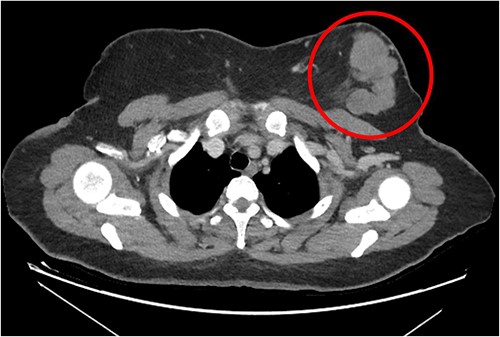

The patient was referred to medical oncology clinic. On exam, she had an eastern cooperative oncology group-performance status of zero, was in pain from her left breast. Assessment of the breast lump revealed a palpable, huge left breast mass, hard in consistency, around 10 cm in largest diameter. There were no palpable lymph nodes in the left axilla. Examination of the right breast was unremarkable. The affected breast is shown in Fig. 1. Otherwise, her chest and abdomen exam were unremarkable, with no lower limb edema. Baseline chest-abdomen–pelvis computed tomography (CT), shown in Fig. 2, showed a large left breast mass 8.0× 2.0 × 4.7 cm with diffuse skin thickening, few axillary lymph adenopathy, the largest of which measured 1.9 cm (shown in Fig. 3), with no distant metastasis. No magnetic resonance imaging was obtained prior to treatment as it was unavailable at the institute. The case was discussed by a multidisciplinary team of medical oncologists, radiation oncologists, surgical oncologists and pathologists. The final decision was that the patient should be treated as a case of high-grade sarcoma, so she was started on ifosfamide–adriamycin (IA) protocol (ifosfamide, 2500 mg/m2, mesna, 800 mg/m2 and doxorubicine, 75 mg/m2 intravenous (IV) for 3 days) as neoadjuvant, to be followed by surgery and adjuvant radiotherapy and chemotherapy. Paraffin blocks were requested by the pathologists for case revision at our institute.

Left breast mass along with involved axillary lymph nodes, encircled.